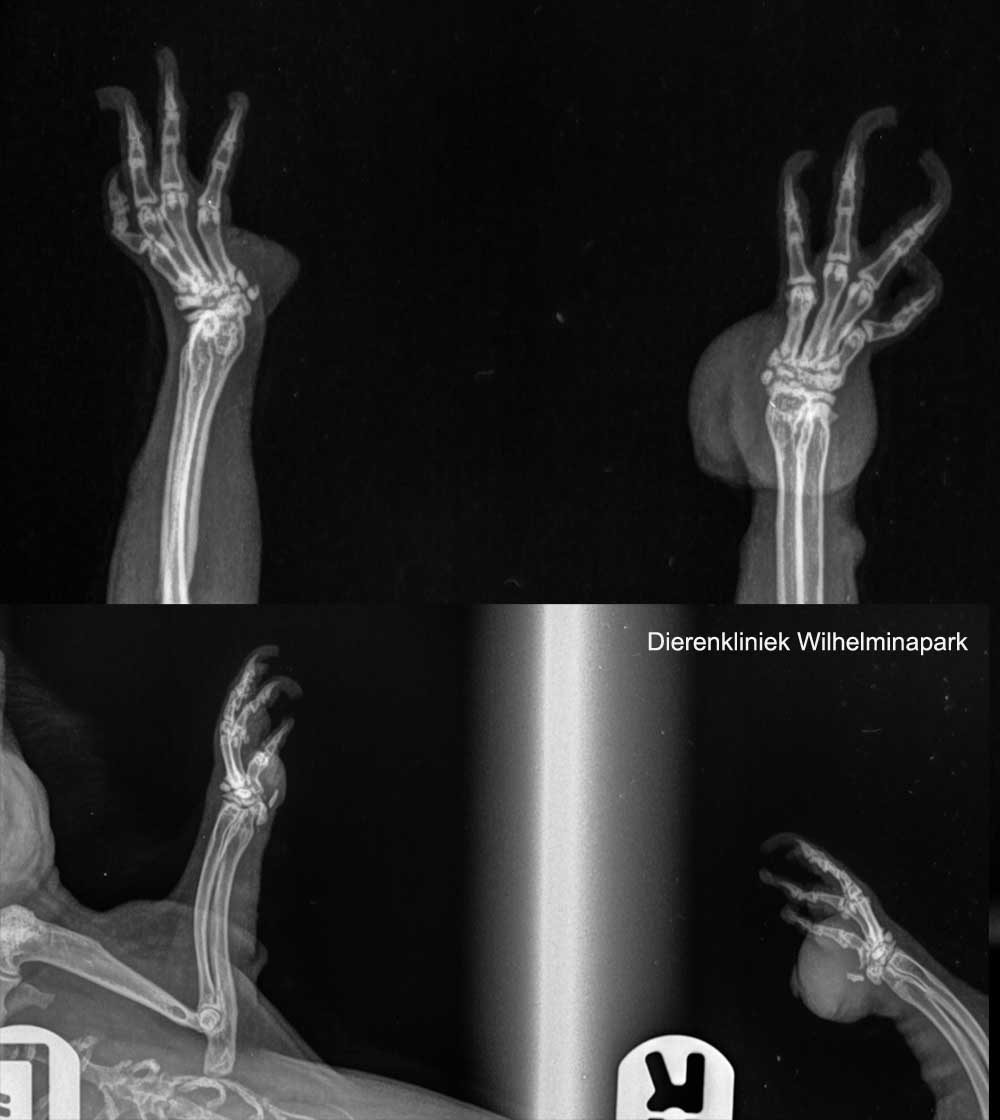

Bij cavia Brownie was er een sterk verdikte rechter voorpoot.

We hebben een röntgenfoto gemaakt, er was een weke delen zwelling, maar geen botaantasting.